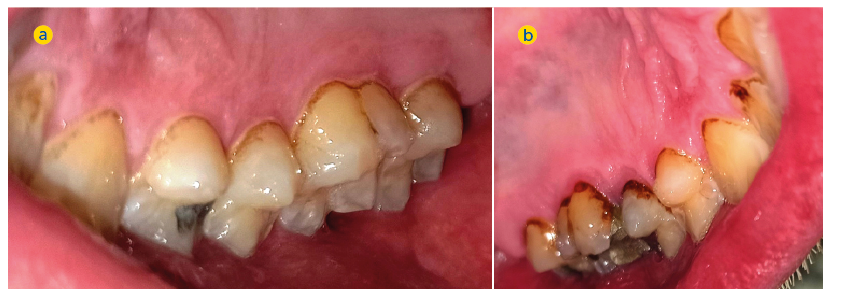

Deutlich stärkere Schmelzdemineralisationen, White spots und Zahnhalskaries auf der paretischen Seite (2. Quadrant, Abb. 5b) als auf der nicht paretischen Seite (1. Quadrant, Abb. 5a)

Deutlich stärkere palatinale Zahnverfärbungen und Zahnsteinablagerungen auf der paretischen Seite (2. Quadrant, Abb. 6b) als auf der nicht paretischen Seite (1. Quadrant, 6a)

(p = 0,032; s. Tab. 3), was auf eine schlechtere Gingivagesundheit hinweist. Darüber hinaus war die Prävalenz unbehandelter kariöser Läsionen auf der paretischen Seite höher als auf der nicht paretischen Seite

(s. Tab. 3). Ein Fallbeispiel illustriert eindrucksvoll die Unterschiede zwischen der kariesfreien nicht paretischen Seite und der paretischen Seite mit multiplen aktiv kariösen Läsionen (Abb. 5a und b). Zusätzlich wies die paretische Seite eine höhere Anzahl an Restaurationen auf als die nicht paretische Seite (s. Tab. 3). Hinsichtlich des Zahnsteinbefalls wurden auch im Seitenvergleich der Mundhälften keine signifikanten Unterschiede zwischen den paretischen und den nicht paretischen Seiten festgestellt. Im Einzelfall wurden jedoch eindrucksvolle Unterschiede zwischen beiden Mundhälften deutlich (Abb. 6a und b).